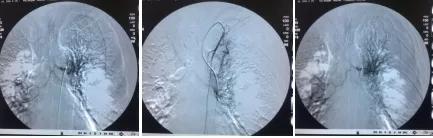

1个月后张爷爷来院复诊,复查胸部CT提示:左肺上叶肿块缩小到1cm,肺不张明显缓解,胸腔积液减少 。 张爷爷表示近1月来态势明显好转,未再咯血,活动也不像之前那样一动就喘,平时走路吃饭都不影响。入院后PS评分1分,临床疗效评估为PR。 为更好的控制肿瘤,进行了第二次介入治疗。 行支气管动脉及胸廓内动脉造影后显示肿瘤染色明显减少,继续灌注化疗药物后,将肿瘤滋养动脉进行了彻底栓塞。 术后无不适, 顺利完成第二次治疗。

第一次介入造影显示肿瘤供血动脉及肿瘤染色

第二次介入造影显示肿瘤供血动脉减少及肿瘤染色明显减轻